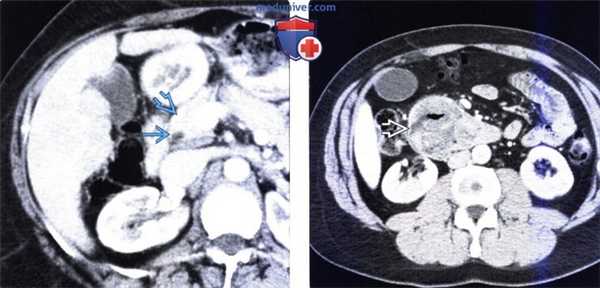

(Слева) На аксиальной КТ с контрастным усилением, выполненной мужчине 49 лет с жалоба -ми на боль в животе и нарушением функции печени, определяется расширение внутрипеченочных желчных протоков.

(Справа) На аксиальной КТ с контрастом определяется также расширение панкреатического протока. Эти изменения позволяют предположить злокачественное новообразование, расположенное в Фатеровой ампуле или возле ее, которое и послужило причиной обструкции.

(Слева) На аксиальной КТ с контрастным усилением у этого же пациента определяется, что головка поджелудочной железы не изменена, в то время как общий желчный проток: в дистальных отделах остается расширенным.

(Справа) На аксиальной КТ с контрастом у этого же пациента определяется большое объемное образование в просвете второй и третьей части двенадцатиперстной кишки, которое обусловливает обструкцию протоков в области относительно низко расположенной Фатеровой ампулы. При эндоскопическом исследовании был подтвержден рак двенадцатиперстной кишки, развившийся в ворсинчатой аденоме.